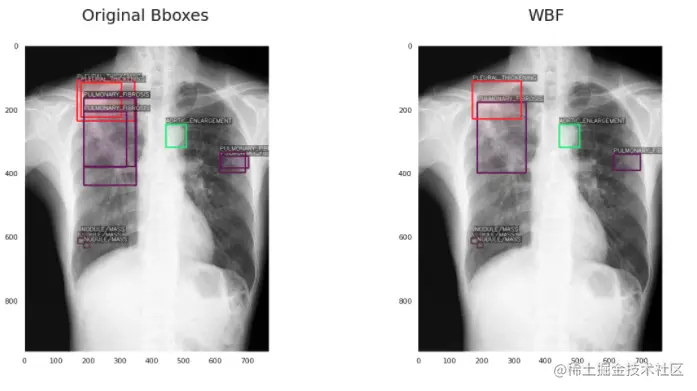

给大家介绍一下背景,这个比赛是关于用x光检查肺部疾病的。你的模型必须能够区分14种不同的疾病,并且对每种疾病预测出疾病所在的边界框。这变得更加困难,因为每个图像可能有不止一种疾病(因此你必须预测多个不同的边界框)。

第一个问题是,这些疾病是由多个不同的放射科医生标记的,对于同一种异常可能有多个不同的边界框。所以我们必须过滤这些(或者在本例中“融合”它们),以避免混淆我们的模型。

第二个问题是一些密集疾病区域包含多个标签,这意味着一个小的包围框可以有多个疾病标签。如果我们使用像NMS这样的东西,会很困难,因为我们是根据IoU过滤框。因此,像NMS这样的方法很可能会删除有用的框。

我将讨论每一种技术,包括使用该技术之前和之后的边界框的可视化。

3、加权框融合 (WBF)

WBF算法的工作方式与NMS不同。它有点长,而且确实涉及到很多数学方程,但我将尽我最大的努力给你一个简单的概述,而不是让你厌烦的细节。

首先,它将所有边界框按照置信度分数的递减顺序进行排序。然后,它生成另一个可能的框“融合”(组合)列表,并尝试检查这些融合是否与原始框匹配。它通过检查IoU是否大于指定的阈值(hyperparameter)来实现这一点。

然后,它使用一个公式来调整坐标和框列表中所有框的置信度分数。新的置信度仅仅是它被融合的所有框的平均置信度。新坐标以类似的方式融合(平均),除了坐标是加权的(意味着不是每个框在最终融合的框中都有相同的贡献)。权重的值由置信度决定,这是有意义的,因为较低的置信度可能表明预测不正确。

图片